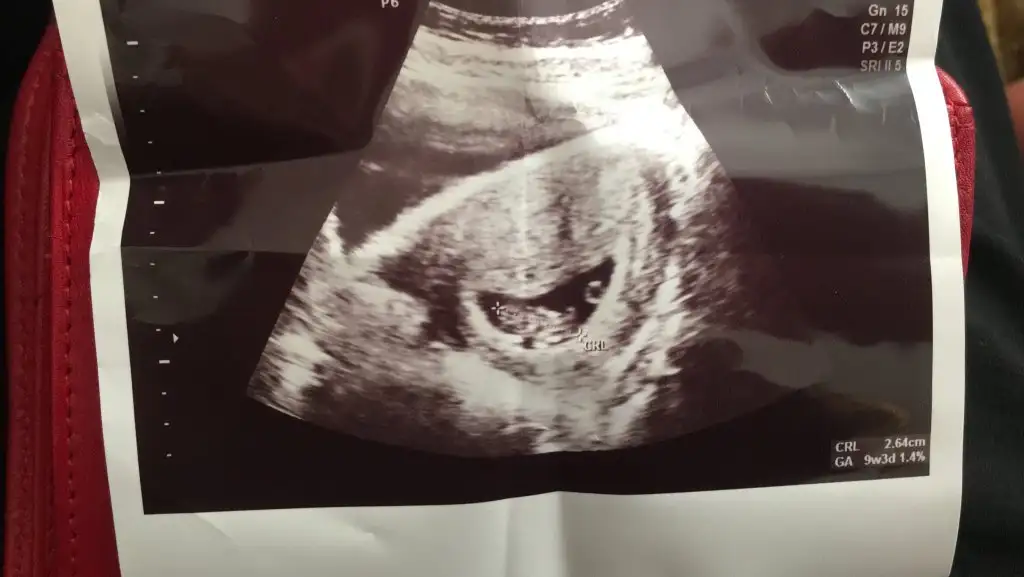

Erkek gibi sanki emin olamadımBende yorum alabilir miyim acaba

Kaç haftalık USG 11 12 13 haftalar olmalı nub görünmüyor başka USG varsa paylaşın